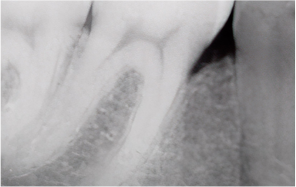

Periodontitis — commonly known as gum disease — is one of the most prevalent conditions

that destroys the gingiva and alveolar bone.

It begins with simple gum swelling

and bleeding,

but if left untreated, the alveolar bone gradually resorbs,

ultimately leading to tooth extraction.

Moderate–Chronic Periodontitis

Tooth mobility increases; gingival recession exposes tooth roots